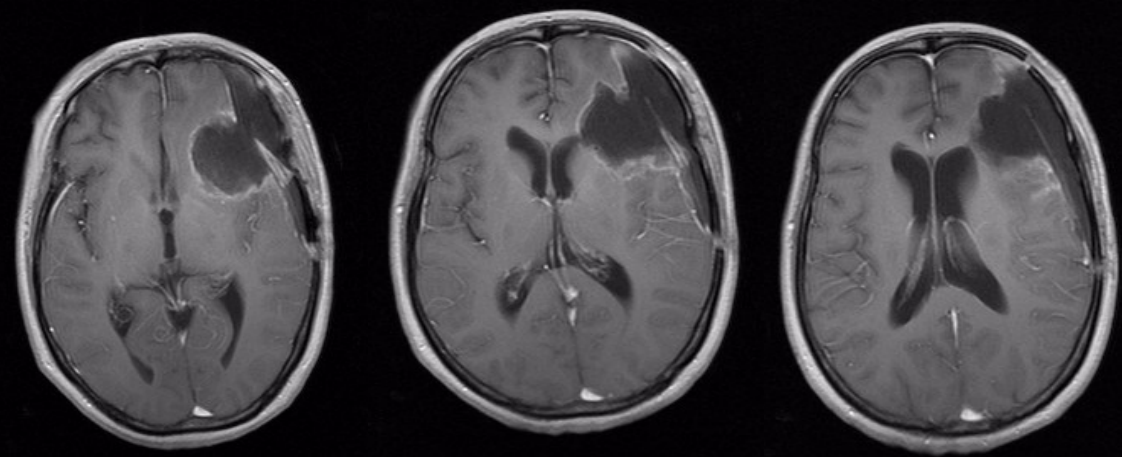

术前头颅MRI平扫加增强